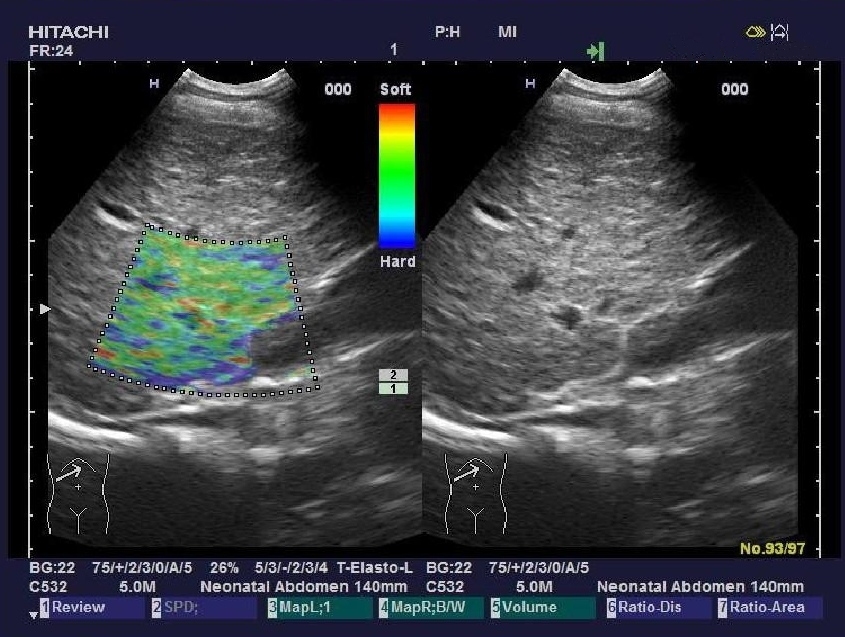

實時組織彈性成像技術(shù)

(Real-time Tissue Elastography)

“ARIETTA 70”加載了彈性成像功能,實時組織彈性成像技術(shù)是根據(jù)人體不同組織受壓后的變形差別,將其不同的組織的彈 性系數(shù)差異用不同的彩色顯示出來的新成像診斷技術(shù)。

組織彈性成像技術(shù)完全脫離了常規(guī)超聲聲阻抗成像原理,開辟了超聲診斷原理的新領(lǐng)域。將指尖的觸診高速信息化數(shù)字化,不 僅實現(xiàn)了定性分析,還具備定量分析功能。

臨床應(yīng)用領(lǐng)域:乳腺、甲狀腺、前列腺、皮膚、肝臟、子宮、卵巢、胰 腺、淋巴結(jié)、血管、直腸、睪丸、顱腦及多種術(shù)中檢查。